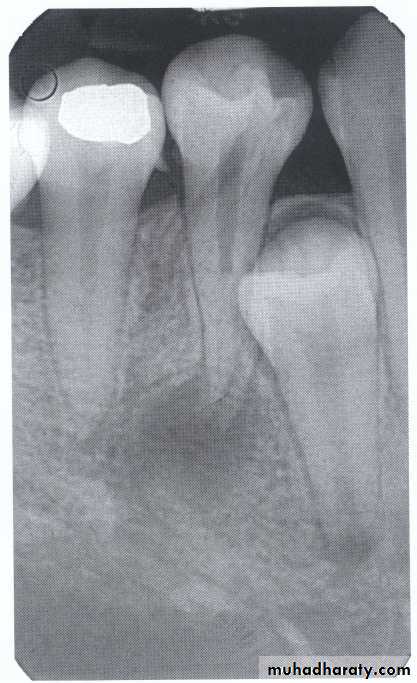

Dilacerated root. The apical portion of the root is bent buccally or lingually into the plane of the central ray. Note the halo in the apical region, produced by the PDL

space (arrow).